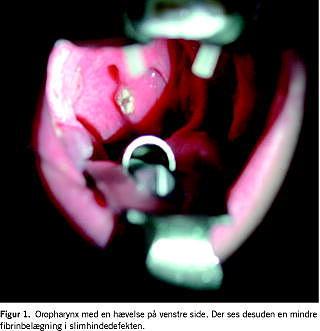

Senere samme døgn lagde man patienten i generel anæstesi med henblik på regelret incision og drænage af absceskaviteten. Der blev placeret en standard Boyle-Davis-gag, og oropharynx blev inspiceret. Her så man i patientens venstre side en hævelse på ca. 3 × 2 × 1 cm med defekt slimhinde i et område, der var få millimeter i diameter (Figur 1 ). Palpatorisk forsøgtes eksprimering af pus, men hævelsen var fast af konsistens og uden fluktuation. Samtidig fremkom hjørnet af et fremmedlegeme i defekten. Fremmedlegemet fattedes med péan , og defekten blev udvidet med en skalpel, således at fremmedlegemet kunne fjernes in toto fra kaviteten. Det viste sig, at der var tale om et glasskår af overraskende størrelse (Figur 2 ), skarpt på alle fire kanter, men i øvrigt uden særlige kendetegn. Kaviteten blev gennemgået uden yderligere fund og blev i øvrigt efterladt åben for at undgå sekundær infektion. Der var ingen peroperativ blødning og intet pus i kaviteten. Operationen afsluttedes uden yderligere tiltag.